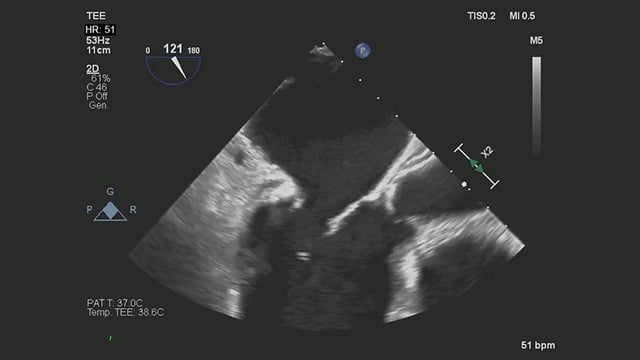

How should I manage a patient with insufficient surgical closure of the left atrial appendage

Incomplete surgical LAA closure: how would you proceed?

Despite prior closure with an Atriclip during CABG, transoesophageal echocardiography reveals a persistent LAA gap in a high-risk patient with recurrent bleeding.

Explore the clinical details, imaging, and treatment dilemmas—then share your management approach!